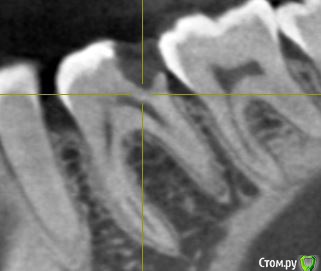

Сделала КЛКТ для того чтобы посмотреть насколько близко к пульпе располагается пломба. Однако материал данной реставрации оказался нерентгеноконтрастным. Так что только такой снимок зуба.

Также прилагаю снимок до лечения (там реставрация видна).

post-57670-0-35912200-1559650995_thumb.jpg